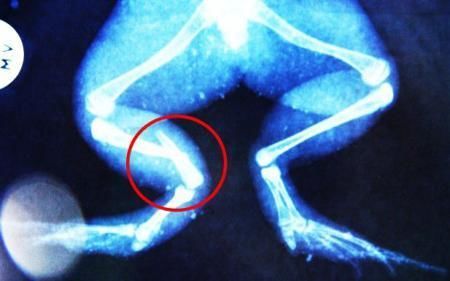

環球網4月2日報道 據《每日郵報》報道,上個月,南非大牛蛙布魯萊的右小腿被鄰居家的一只狗咬到,導致粉碎性骨折,現在經過2個小時的手術,它的斷腿已經被接上,它也因此成為有史以來第一只通過外科手術用鋼針接上斷腿的青蛙。

布魯萊的主人,居住在南非約翰內斯堡附近的62歲的安妮·米恩斯說:“我對這只青蛙如此關心,人們一定認為我瘋了,但是我無法眼睜睜看著它那么痛苦。青蛙因其靈活的腿腳而著稱,一想到布魯萊的腿里要留下一個薄金屬片,我就感到心痛。然而我知道,如果不進行手術,布魯萊以后就沒辦法動彈了。因此我匆匆趕到獸醫那里,央求他給這只可憐的青蛙動手術。這位獸醫整天救助小貓小狗,他很難理解為什么我這么擔心一只青蛙,但是最終他還是答應了給布魯萊做手術。手術后是幾個小時的焦急等待,我們希望它能快快蘇醒過來。不過現在它的傷口已經愈合,又能在花園里跳來跳去了。X光照射顯示,它會恢復的跟以前一樣!

野生生物專家安妮經常為學校寫教材,她認為這是人類第一次通過手術給一只青蛙接斷腿。在手術開始階段,獸醫把少量給狗用的麻醉藥注入到這只青蛙體內,讓它失去知覺。然后他在布魯萊的斷腿上切開一個小口,把一根小鋼針植入腿里。最后獸醫給它縫了9針,把切口縫合在一起。僅僅幾周后,布魯萊就能在安妮家附近活動了。這只青蛙大約已有25歲,主要以嚙齒動物、蛇和其他青蛙為食。布魯萊所屬的牛蛙種群正在不斷減小,目前只能在非洲南部的濕地里才能看到這種青蛙。